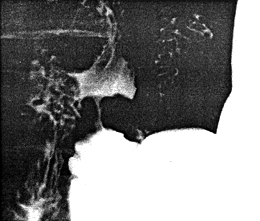

![]() |

| Fig. 13.2. Four monophasic duodenal pressure waves. Each was associated with a radiologically visible contraction. During each wave mucosal folds changed in direction to become longitudinal. Base line indicates intraluminal pressure in absence of motor activity. Ten-second marker on zero line |